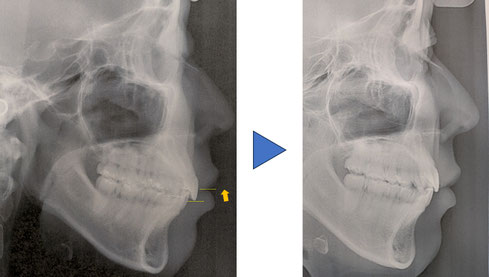

主訴:前歯が出ている。歯がデコボコしている。

治療開始時年齢:16歳 マルチブラケット装置と上顎にアンカースクリューを用い、上下顎両側第一小臼歯を抜歯して矯正治療を行った。動的治療期間:約2年間 装置を撤去し保定へ、保定期間は約2年。歯並びと口元の突出感は改善した。治療費は、80万円。